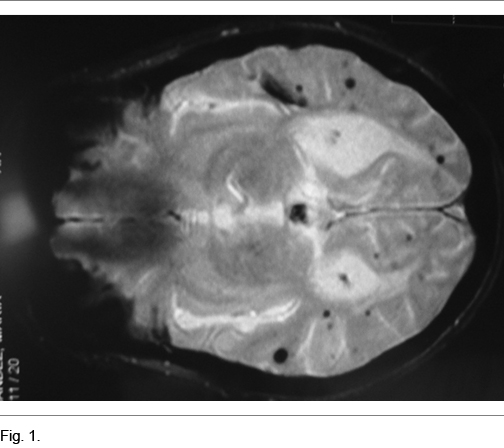

Se planteó síndrome demencial rápidamente progresivo (DRP) y solicitó RNM que muestra múltiples imágenes anormales de diferentes tamaños a nivel subcortical y cortical, hipo intensas en T1 híperintensas en T2, que corresponden a pequeñas hemorragias corticales y subcorticales evolucionadas (Figuras 1 y 2).

La AAC debe ser sospechada clínicamente en pacientes mayores de 60 años con hemorragias cerebrales múltiples en ausencia de una causa evidente (5). En la Resonancias Magnética Nuclear (RNM) es característica la presencia de imágenes compatibles con microsangrados difusos como en este paciente, así como depósitos de hemosiderina.